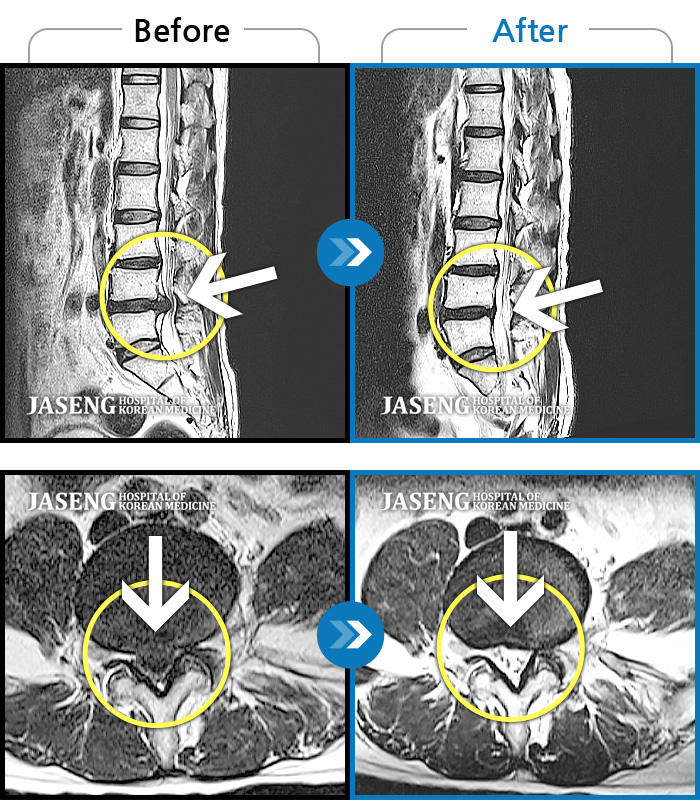

ȯںп  Ǹ   ǿ ԿǾ, ο  ġ  ۿ     Ƿ   ġḦ Ͻñ ٶϴ.